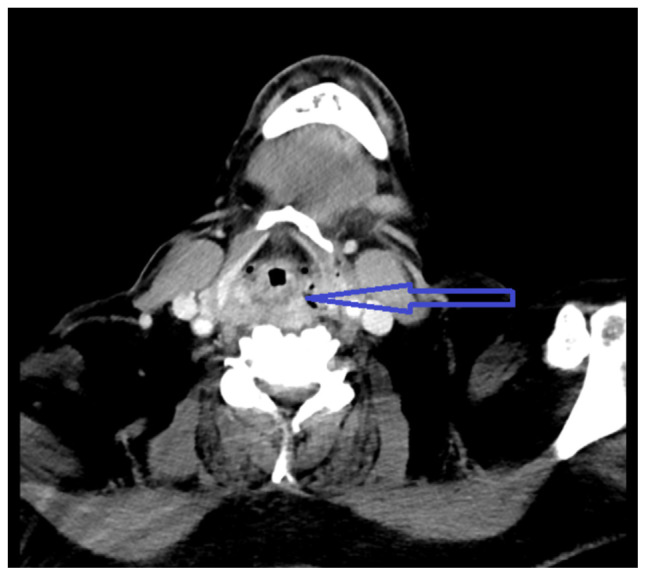

Transesophageal echocardiography is a relatively safe procedure; however, there are rare complications associated with it. Multiple attempts during TEE can lead to injury of hypopharyngeal or parapharyngeal wall leading to an infection. Here, we describe a case of hypopharyngeal-parapharyngeal abscess resulting from multiple TEE attempts during cardioversion leading to a prolonged hospital course.